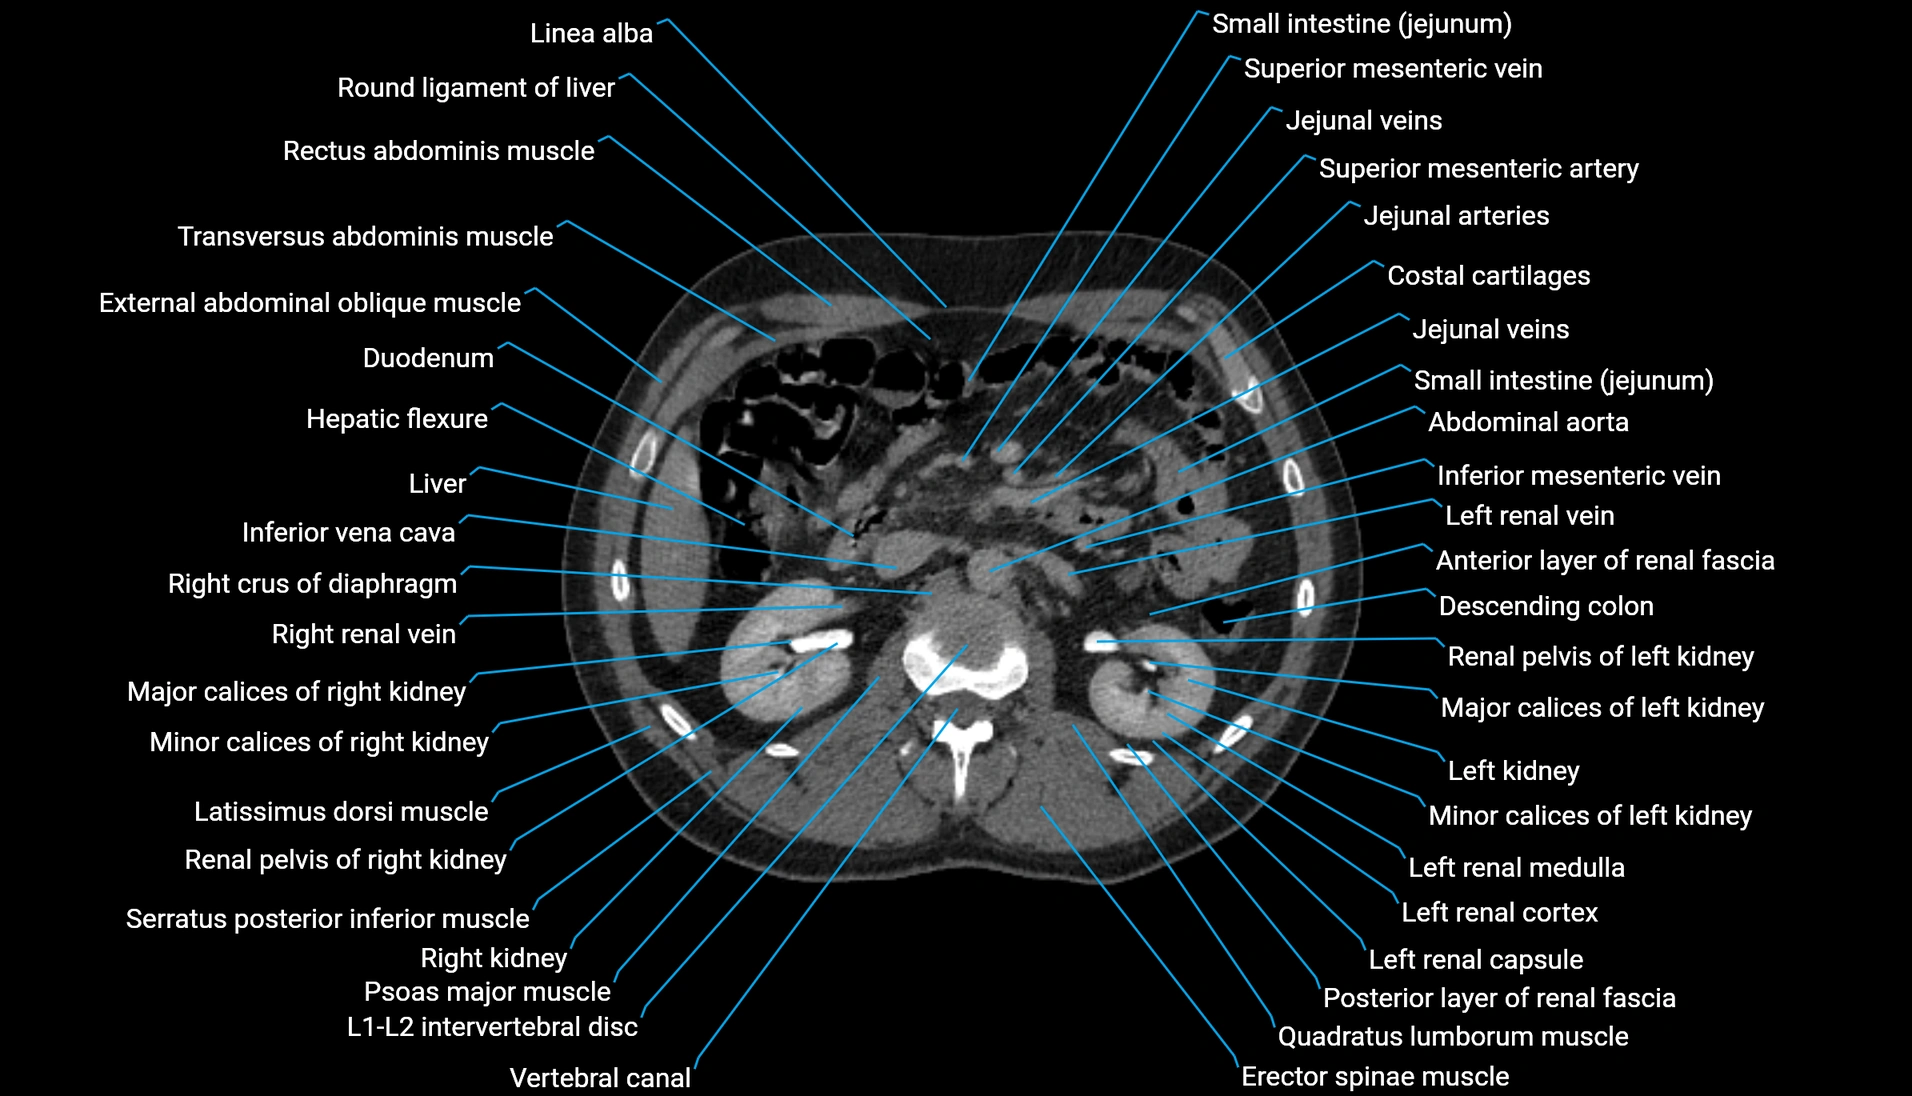

CT Appearance

Non-contrast CT:

-

Demonstrates cortical bone of acetabular rim in excellent detail

Detects fractures, dysplasia, retroversion, or bony overcoverage (pincer impingement)

3D reconstructions used in preoperative hip surgery planning

CT VRT 3D image

CT image